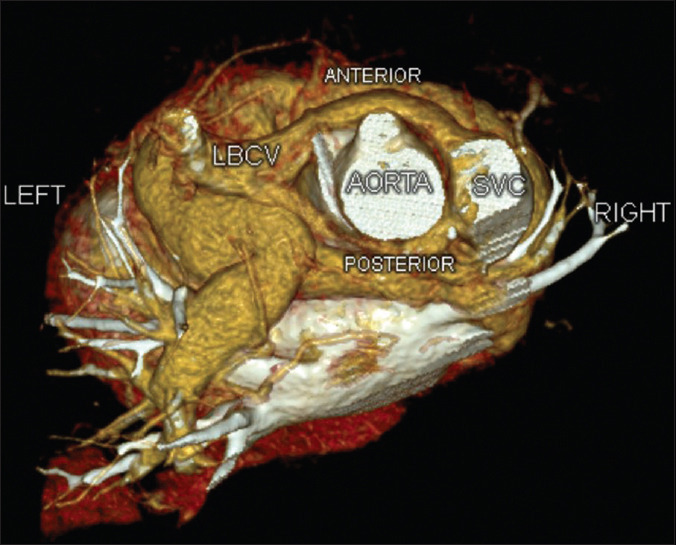

The left brachiocephalic vein (LBCV) usually passes superior and anterior to the aortic arch. In rare cases, this vein follows an anomalous course. We present a case of duplicated circumaortic LBCV in a 10-year-old child with Tetralogy of Fallot.